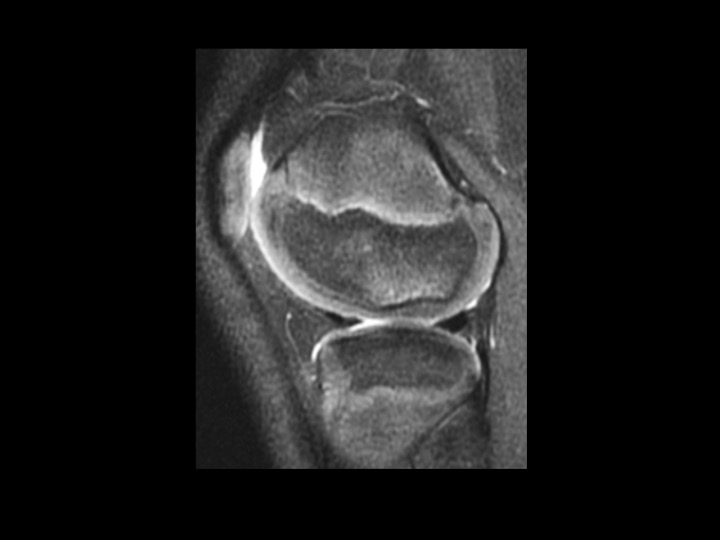

9M fell 3 weeks ago, evaluate osteochondral lesion

The subchondral cortical flattening and minimal subchondral bright T2 signal with smooth, relatively thick overlying articular cartilage is not related to the injury 3 weeks prior. I considered possible chronic stable OCL, but I believe this looks like the normal variant ossification in the attached article. Any dissent? Reference article.

normal developmental irregular ossification lateral femoral condyle